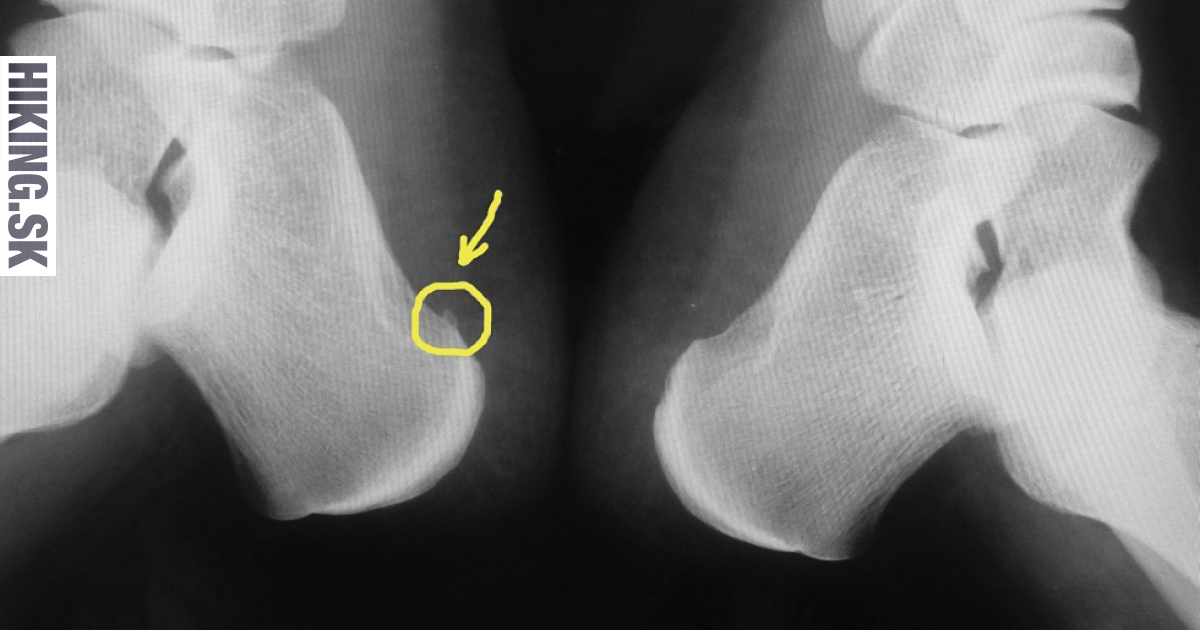

Ľudovo povedané ide o výrastok - kalcifikát na šľache, respektíve úpone zospodu päty. Doktori hovoria o Plantárnej fascitíde (Plantárna fascia - veľká šľacha v chodidle vedúca od päty k prstom). Nezamieňať si s výrastkom vzadu na päte na achillovej šľache. Na RTG snímke je jasne vidieť kalcifikát v tvare ostrohy, respektíve tŕňa. Teraz si už každý vie predstaviť ako sa po dačom takom „dobre“ chodí. Pričom nezáleží na veľkosti výrastku. Stáva sa, že ľudom vôbec neprekáža, ale keď si nájde správne miesto, správny nerv, tak sa dráždené miesto zapáli a potom ho pocítime. Najskôr sa problém spočiatku prejavuje mierne. Ráno s bolesťou došľapujeme na nohu. V priebehu dňa symptómy ustúpia, takzvane sa to rozchodí. Ďalšie ráno sa nepohodlie ale opakuje. Príznak môže byť aj taký, že sa cítime, ako keby sme včera behali po betóne v tenkých šľapkách alebo naboso. Keď sme boli deti, stávalo sa, že nás tak päty pobolievali, ale o pár dní sme opäť behali bez ťažkostí. Teraz zápal sám neodznie. Problémy sa vyskytujú v každej vekovej kategórií, môžu si ho “uhnať ” tak rekreační bežci, ako aj ľudia dlhodobo stojaci v zamestnaní a, samozrejme, sa nevyhýba ani turistom. Stáva sa, že postupne trpia obe chodidlá.

Prehmataním päty v porovnaní s druhým chodidlom si vieme nájsť bod, ktorý je znateľne citlivejší ako okolie. Pri rozsiahlejšom zápale stačí stlačiť pätu a hneď cítime bolesť. Ako bolo spomenuté, na potvrdenie stačí RTG. Prípadne na zistenie rozsahu zapálenia šľachy, úponu, respektíve okolia výrastku, sa dá použiť aj MR.